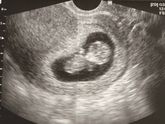

Вчера был скрининг,сегодня я просыпаюсь и опять вижу коричневые выделения. Хотя вчера они сказали,что никакой гематомы вообще не видят ( а ещё неделю назад она была, делала узи в другом месте) Вот я не понимаю, это они так надавили мне,что вышла гематома … Читать далее